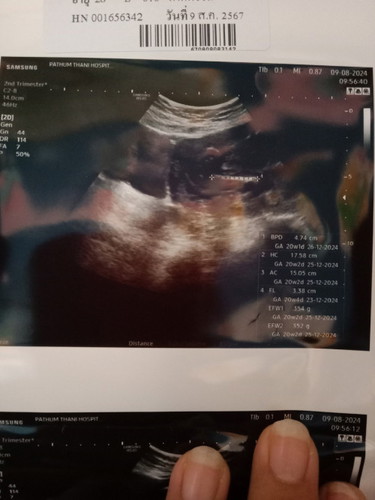

ตั้งครรภ์20+2

อยากทราบว่า แบบนี้น้องหนักเท่ารัย และเพศอะรัย

หนัก 354 กรัม